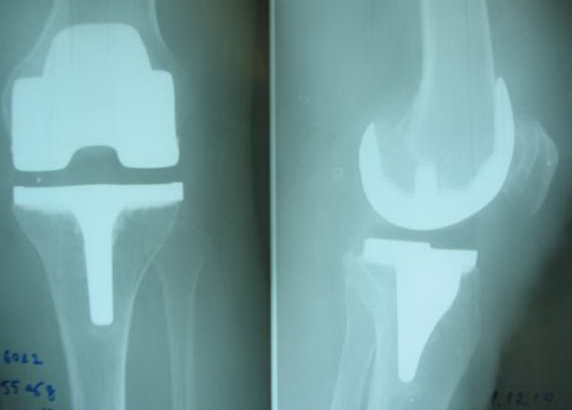

Первичное эндопротезирование коленного сустава

На сегодняшний день общепризнано, что эндопротезирование тазобедренного и коленного суставов является единственным эффективным методом лечения при разрушении суставного хряща и позволяет избавит пациента от боли и вернуть его к активной жизни. В мире ежегодно выполняется более полутора миллионов таких операций. Современные эндопротезы служат десятки лет и позволяют жить полноценной жизнью даже молодым и активным пациентам, а в случае, если эндопротез всё же износился, его можно заменить на более сложный и продолжать пользоваться всеми благами жизни.

Выполняются операции эндопротезирования тазобедренного, коленного, локтевого и плечевого суставов при онкологической костной патологии и посттравматических деформациях.